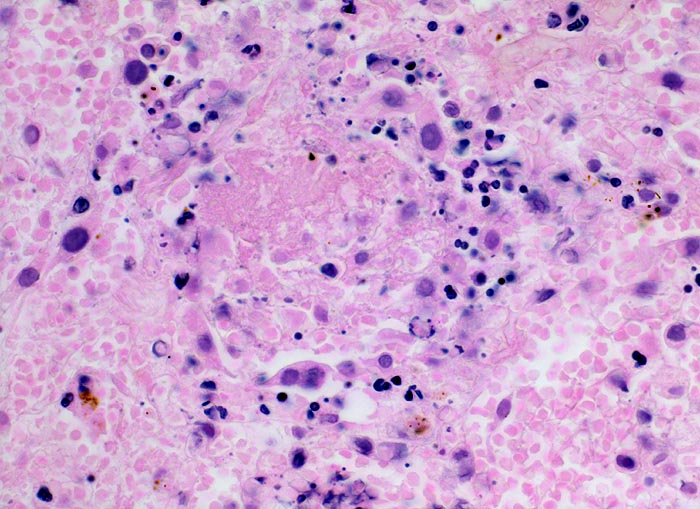

• Scharf begrenzte dreiecksförmige hämorrhagische Nekrose des Lungenparenchyms.

• Alveolen gefüllt mit zerfallenden Erythrozyten, Kerntrümmern und Fibrin.

• Lungengerüst erhalten im Randbereich der Nekrose, nicht mehr erkennbar im Zentrum.

• Abgeblasste Zellkerne in der Nekrosezone.